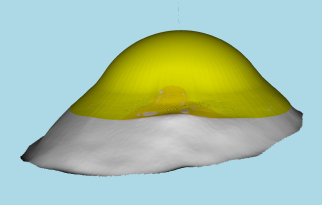

Scleral lenses are large diameter gas-permeable contact lens devices.

Rather than sitting directly on the eye like a traditional soft lens, scleral lenses only touch the sclera (the white part of the eye) and vault entirely over the cornea (the front of your eye - a clear layer of tissue that covers your iris, pupil and lens). This vault - the space between the contact lens and your cornea - is filled with fluid and creates a new, perfect focusing surface.

By vaulting over the eye with fluid, we are able to manage complicated eye conditions such as astigmatism, keratoconus, corneal transplants, severe dry eye, corneal scarring, LASIK complications and more. These lenses can be life changing.